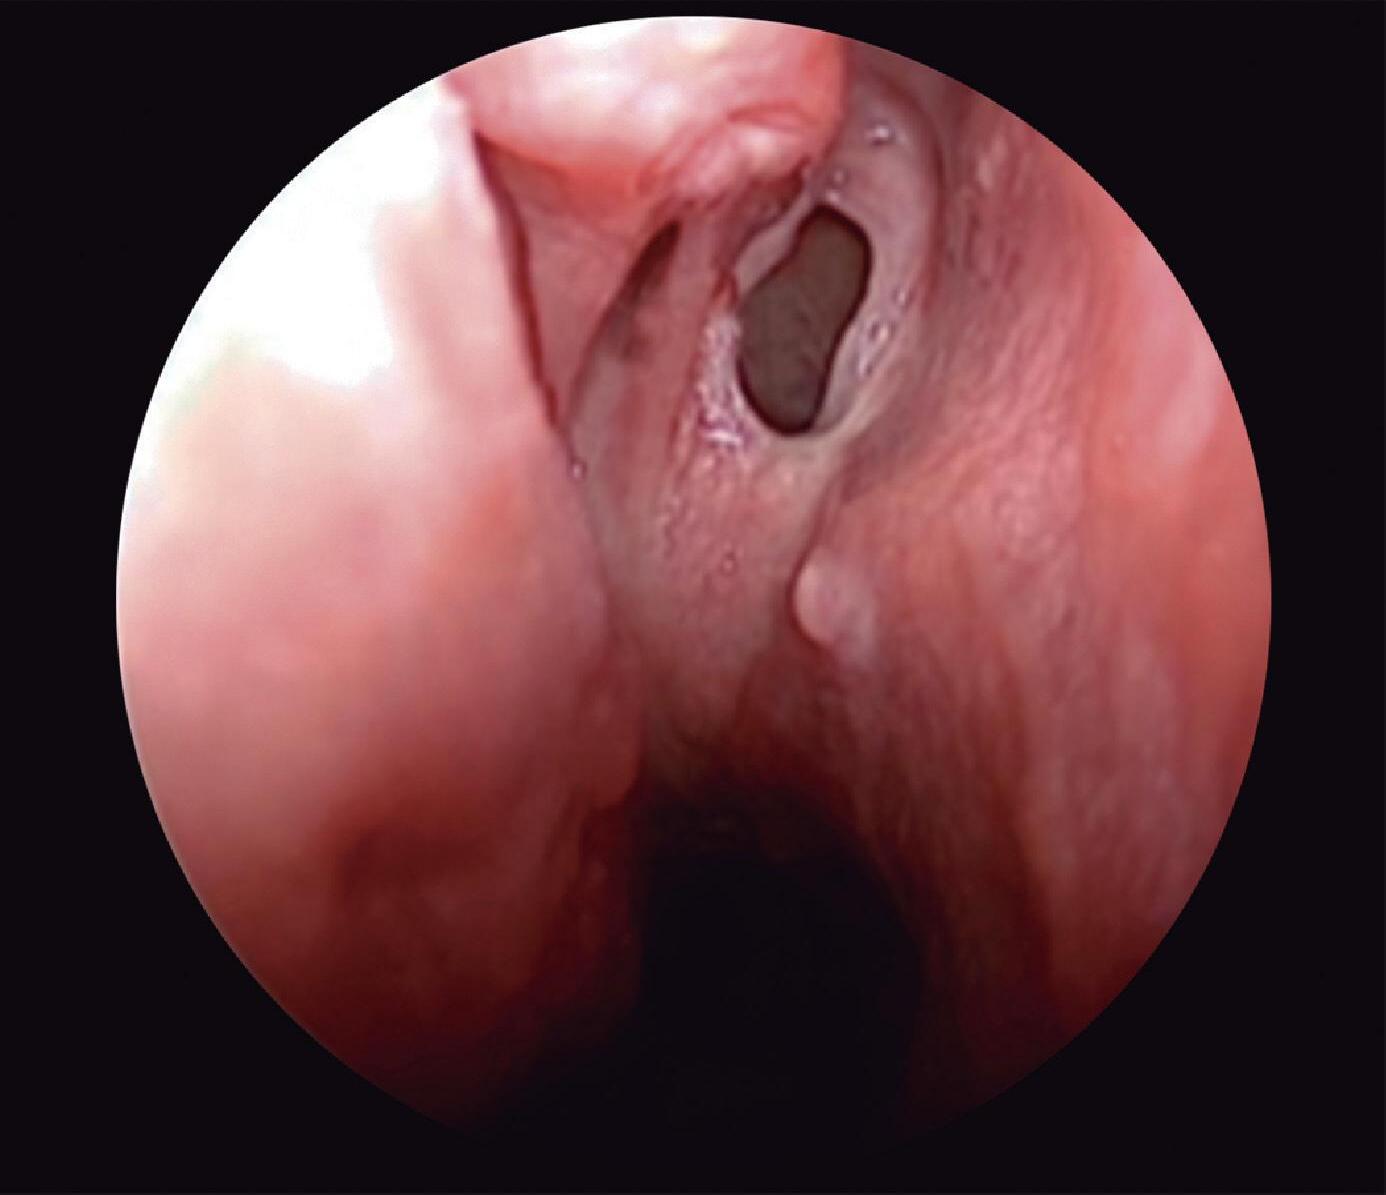

Situado acima do dorso caudal da concha média, protegido lateralmente pela concha superior e medialmente pelo septo nasal, está o óstio do seio esfenoidal. O espaço entre estas estruturas é delimitado superiormente pelo plano esfenoidal e aberto inferiormente em direção à coana, constituindo a câmara esfenoidal, que não faz parte da parede lateral.

Fig. 1-24. Visão endoscópica do óstio esfenoidal direito – observar posição medial à concha superior; (1) septo, (2) óstio esfenoidal, (3) concha superior, (4) meato superior.

2 1